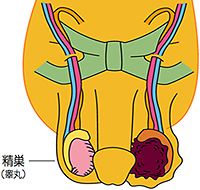

精巣腫瘍を強く疑う場合、基本的に全員に実施される手術です。精巣は血管と精子の通る精管が束になった精索という管でお腹の中とつながっています。精巣がんは、この精索を通り転移することが多く、精巣を摘出する際には陰嚢内の精巣だけでなく、精巣につながっている精索の上の方まで取り除きます。

そのため、摘出する側の下腹部の鼠径部を切って手術を行います。この手術方式を高位精巣摘除術といいます。

高位精巣摘除術の範囲

2.後腹膜リンパ節郭清

後腹膜リンパ節とは、お腹の大血管周囲にあるリンパ節です。精巣腫瘍は始めにこのリンパ節に転移を起こすことが多いため、転移のないⅠ期の場合でも、再発を防ぐ目的でこの部分のリンパ節とその周りの組織を取り去る手術が行われることがあります。

後腹膜リンパ節郭清の範囲

(右精巣腫瘍の場合)